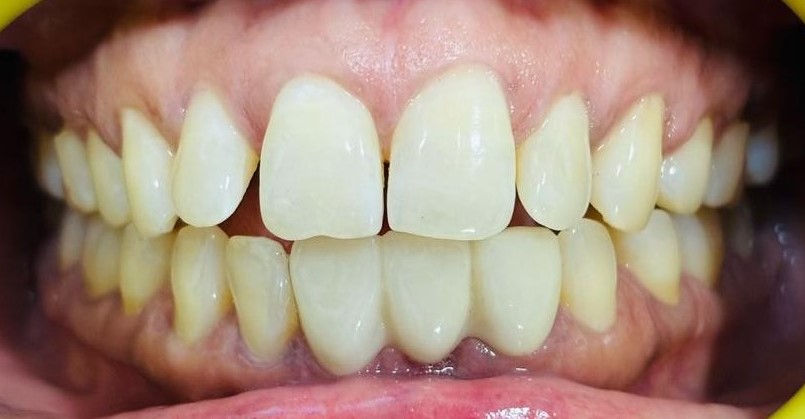

After After